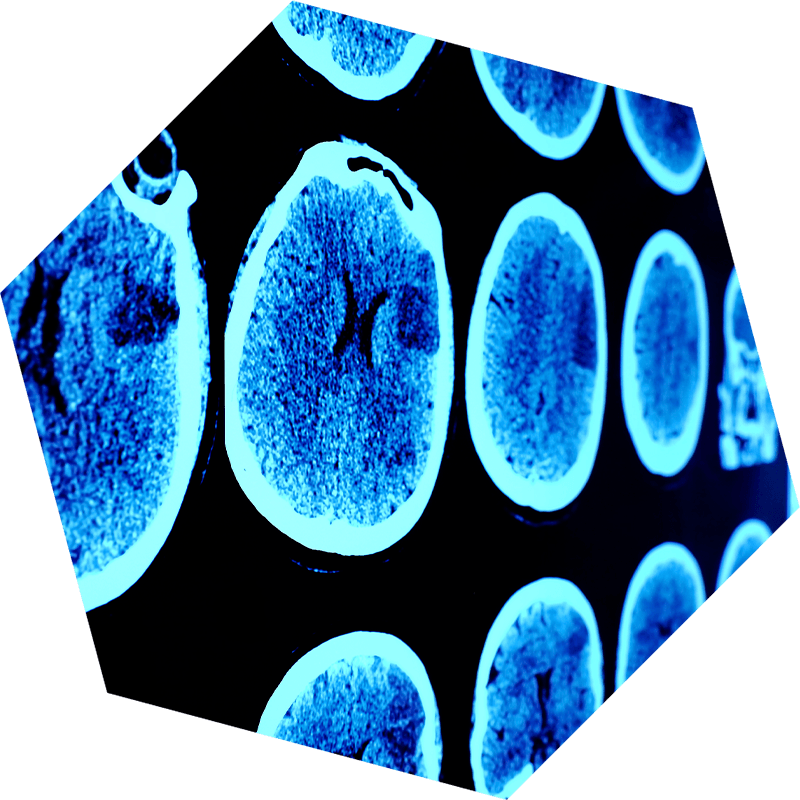

Tomografía Computarizada (TC)

La exploración por tomografía computarizada (TC) o tomografía axial computarizada (TAC) es una prueba indolora que usa rayos X (radiación) para generar las imágenes. El escáner de TC es una máquina abierta, por lo que la claustrofobia no suele ser un problema para los pacientes. La TC suele ser un procedimiento seguro; pero como emplea radiación, el equipo de tratamiento supervisará la exposición frecuente. En los diagnósticos de tumores cerebrales, los escáneres de TC proveen imágenes claras de la anatomía del cerebro, con lo que ayudan a detectar anomalías, tumores, hemorragias y otras afecciones. Al ofrecer una visión rápida y completa, las exploraciones por TC ayudan a los médicos a diagnosticar los tumores cerebrales, evaluando su tamaño, ubicación e impacto en los tejidos que los rodean.